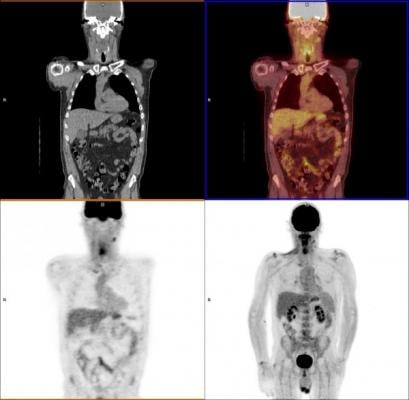

The use of positron emission tomography–computed tomography (PET-CT) scans for image-guided surveillance meant that routine post-treatment operations were no longer necessary, and can now be better targeted to the right areas in those 20 percent of patients who still have persistent cancer.

Prof. Hisham Mehanna, from the Institute of Head and Neck Studies and Education (InHANSE) at the University of Birmingham, explained, “After treatment, remaining cancer cells play something akin to hide and seek. Our study shows that using this PET-CT scan we can hunt them down, find them and remove them effectively.”